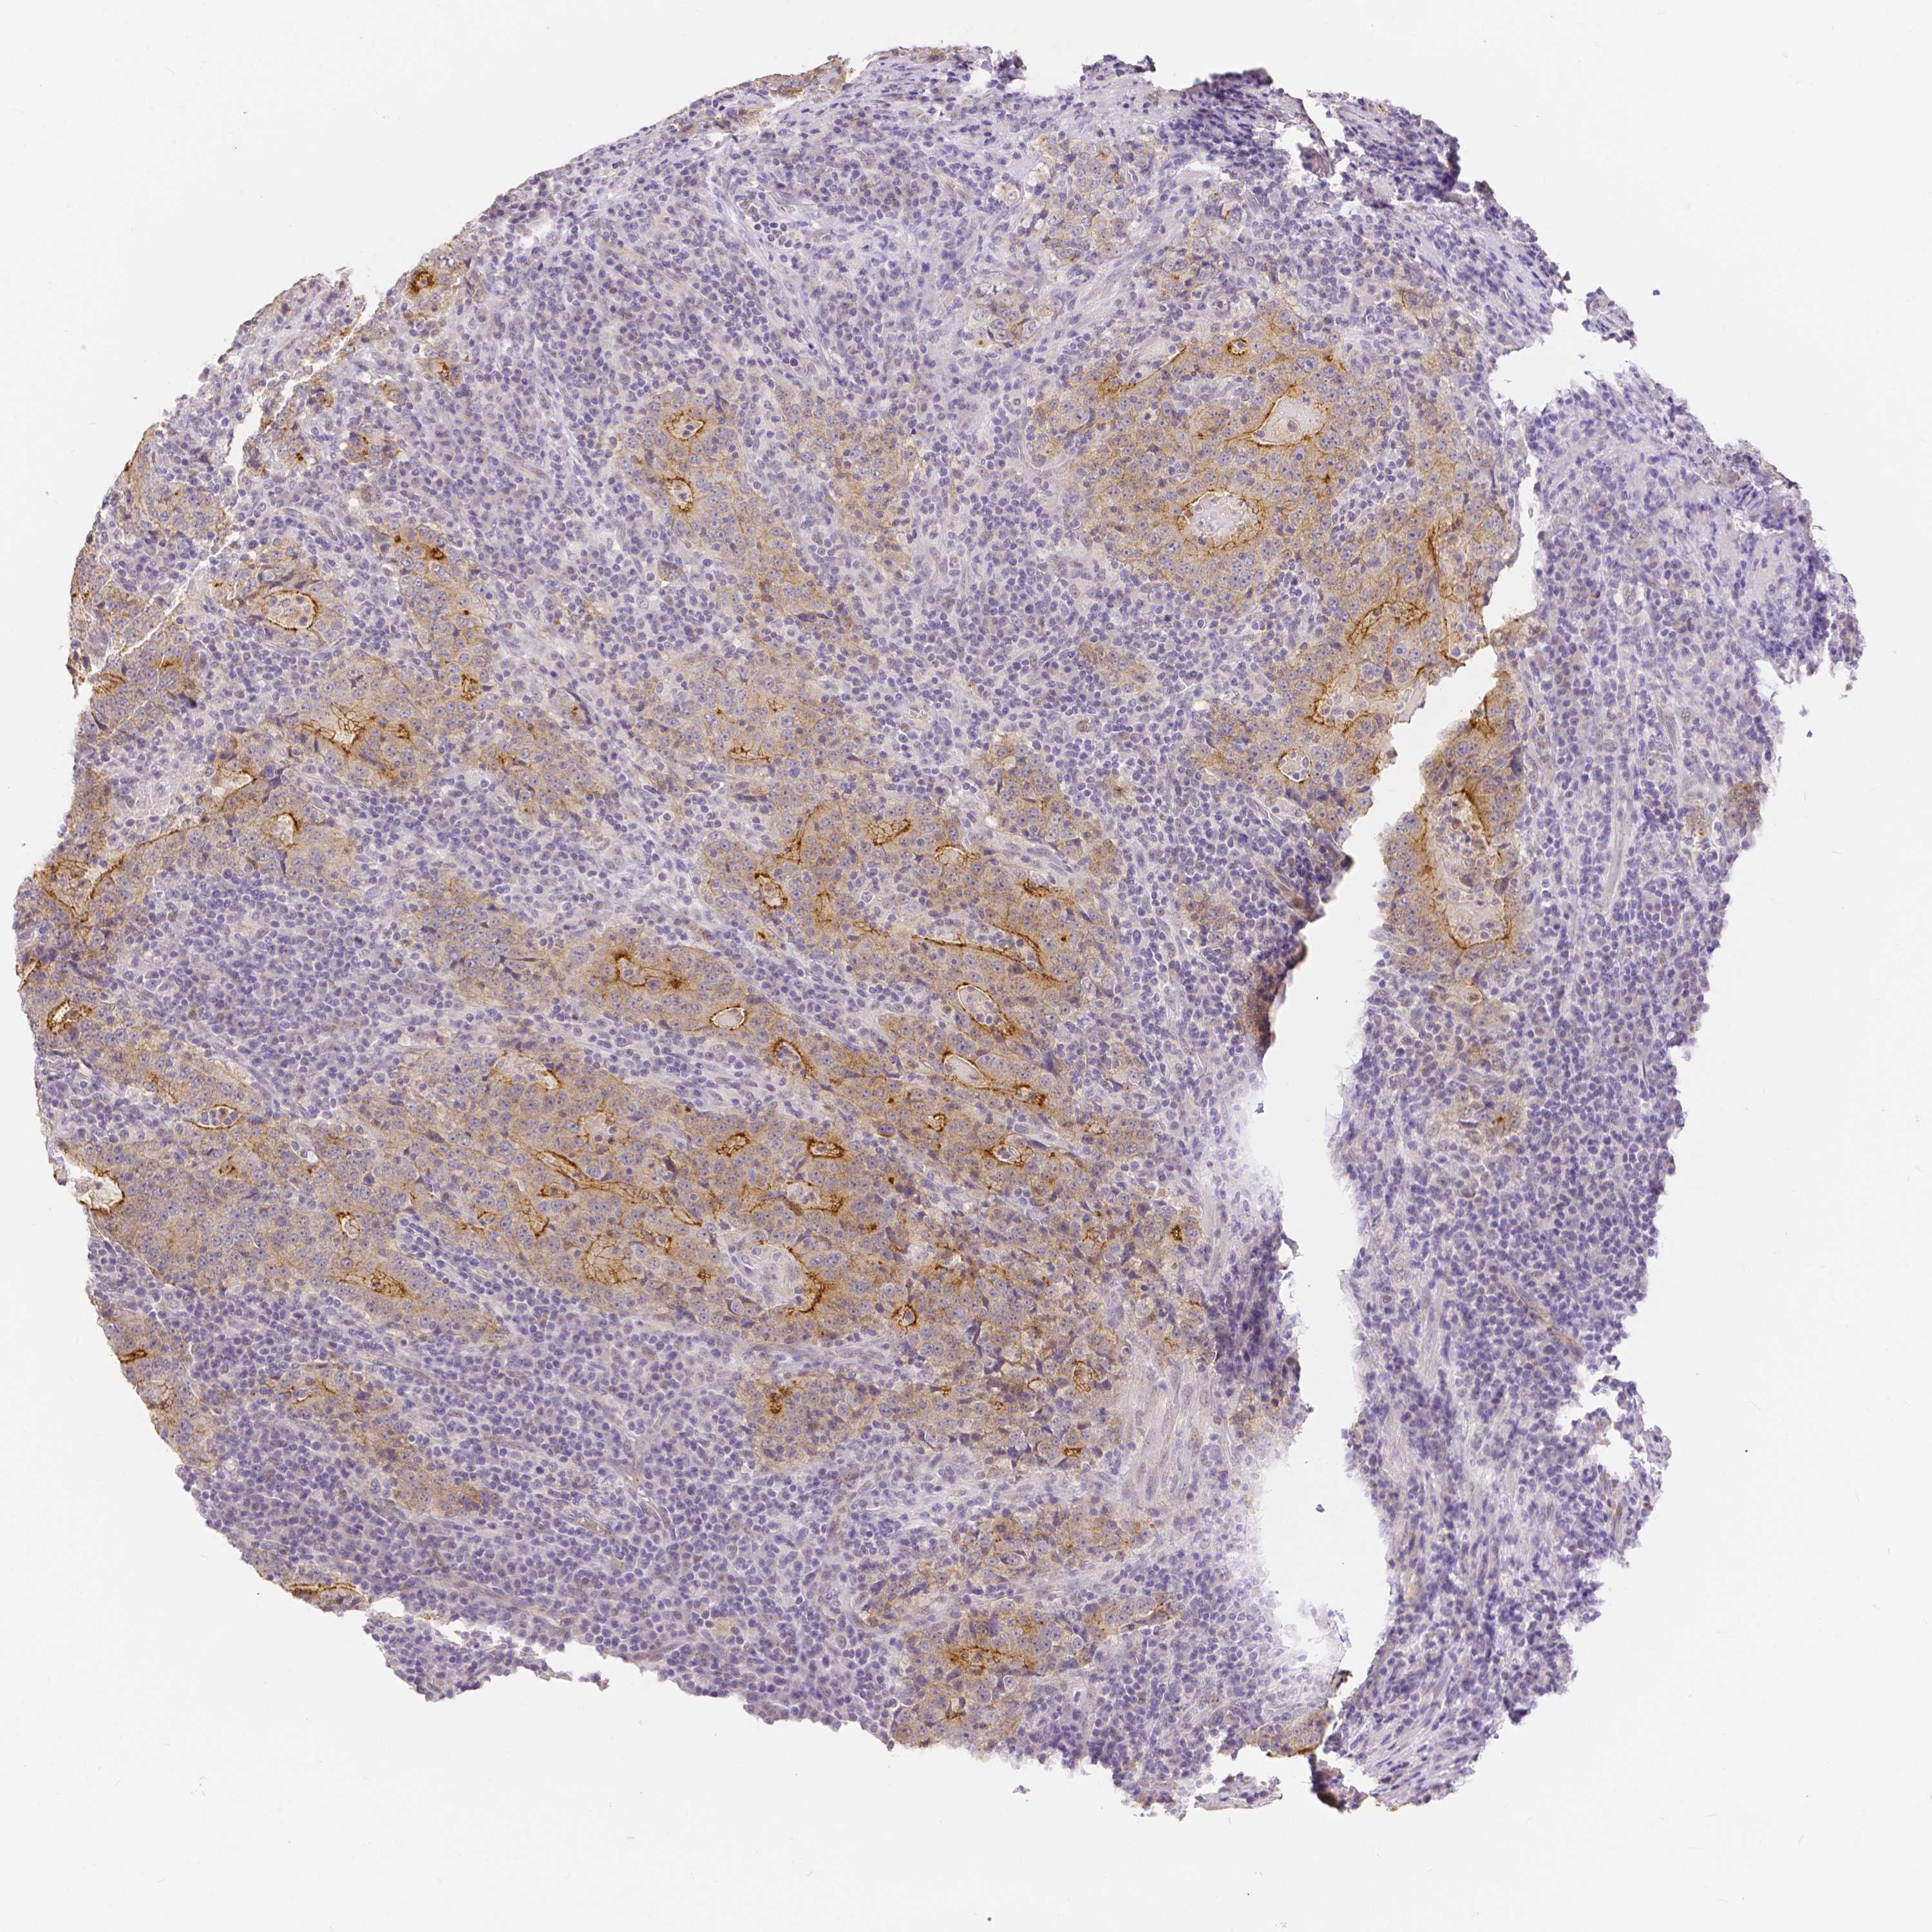

STOMACH CANCER - Protein expressioni

A mouse-over function shows sample information and annotation data. Click on an image to view it in a full screen mode. Samples can be filtered based on level of antibody staining by selecting one or several of the following categories: high, medium, low and not detected. The assay and annotation is described here.

Note that samples used for immunohistochemistry by the Human Protein Atlas do not correspond to samples in the TCGA dataset.

Antibody stainingi

Antibody staining in the annotated cell types in the current human tissue is reported as not detected, low, medium, or high, based on conventional immunohistochemistry profiling in selected tissues. This score is based on the combination of the staining intensity and fraction of stained cells.

Each image is clickable and will lead to virtual microscopy that enables deeper exploration of all samples and also displays staining intensity scores, fraction scores and subcellular localization as well as patient and tissue information for each sample.

HPA005933

CAB013075

CAB068212

CAB068213

CAB068214

Adenocarcinoma, NOS

Adenocarcinoma, High grade